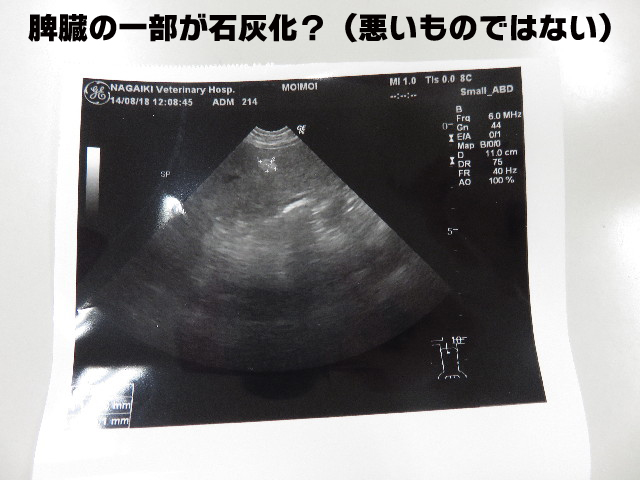

もいちゃん、2週に1度の獣医さんの日でした。

今日は1ケ月毎から2ケ月毎にした『エコー』と『血液検査』もします。

●まずはもいちゃんがキライなエコー。

(獣医さんで仰向けになるのがこわくて緊張してイヤなんです(;□;)!!)

(たしか?)脾臓に石灰化しているみたいなところがあるが、悪いものではないでしょうとのこと。

丈夫の白っぽく写っている豆粒のようなところです。

サイズを測ったので破線も写っています。

他は腎臓、膀胱きれいで、肝臓等も大丈夫(^-^)v